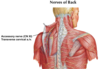

Trapezius

Origin : back of the skull, nuchal ligament, and spinous processes of C7 to T12 vertebrae.

Insertion : lateral third of clavicle, acromion and spine of the scapula.

Innervation : accessory nerve

Blood Supply : superficial branch of the transverse cervical artery

Action : elevation, retraction, and depression of the scapulae. The upper and lower parts working together, elevate the glenoid cavity superiorly.

Recent evidence suggests that the accessory nerve lacks a cranial root and has no connection to the vagus nerve.